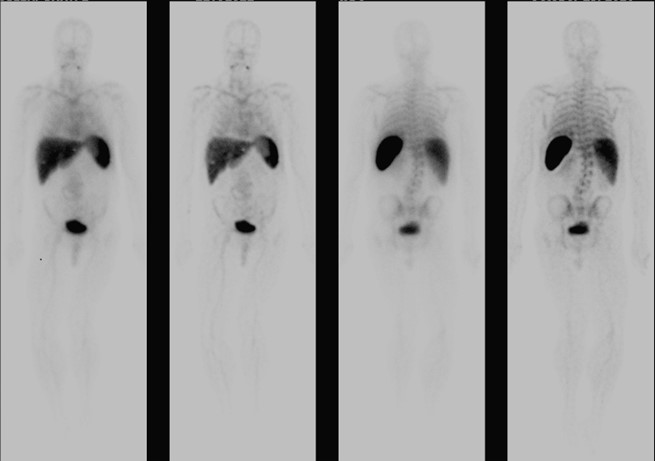

The patient subsequently began to develop abdominal discomfort and new fever spikes. Repeat lab findings showed an increased leukocyte count, and CT angiogram demonstrated a significantly increased size to 7.6 x 9.1 x 13.3cm, concerning for impending rupture and underlying aortitis. Nuclear white blood cell scan was performed and revealed abnormal increased uptake involving the mid and distal abdominal aorta, suggestive of infection. Vascular consultation was obtained, and he successfully underwent percutaneous endovascular aortic repair. He tolerated the surgery well and observed improvement in symptoms, following which he was discharged.

Image 3: Tagged White Blood Cell Scan.